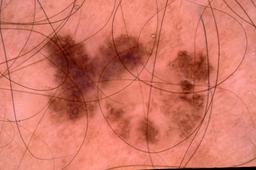

{

"age_approx": 15,

"anatom_site_general": "upper extremity",

"concomitant_biopsy": true,

"dermoscopic_type": "contact non-polarized",

"diagnosis_1": "Benign",

"diagnosis_2": "Benign melanocytic proliferations",

"diagnosis_3": "Nevus",

"diagnosis_4": "Nevus, Congenital",

"diagnosis_confirm_type": "histopathology",

"image_type": "dermoscopic",

"lesion_id": "IL_7863876",

"melanocytic": true,

"patient_id": "IP_3774474",

"sex": "male"